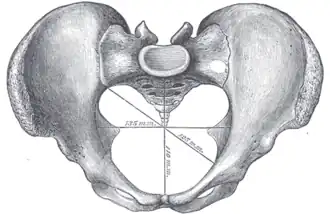

Diameters

The diameters or conjugates of the pelvis are measured at the pelvic inlet and outlet and as oblique diameters.

| Name | Description | Average measurement in female |

|---|---|---|

| Anteroposterior or conjugate diameter or conjugata vera | Extends from the upper margin of the pubic symphysis to the sacrococcygeal joint; | about 110 mm. |

| Transverse diameter | Extends across the greatest width of the superior aperture, from the middle of the brim on one side to the same point on the opposite; | about 135 mm. |

| Oblique diameter | Extends from the iliopectineal eminence of one side to the sacroiliac articulation of the opposite side; | about 125 mm. |

| Anatomical conjugate | Extends from the pubic symphysis to the promontory; | about 120 mm. |

| Diagonal conjugate | Extends from lower margin of the pubic symphysis to the sacral promontory; | about 130 mm. |

| Straight conjugate | Extends from the lower border of the pubic symphysis to the tip of coccyx. The coccyx can bend posteriorly and expand the diameter with 25 mm; | about 95 mm (+ 25 mm). |

| Median conjugate | Extends from the lower border of the pubic symphysis to the lower border of the sacrum; | about 115 mm. |